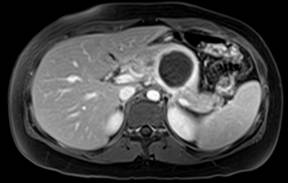

Figure 2. Unenhanced axial abdominal CT scan: hypodense, slightly heterogeneous mass of the body/tail of the pancreas, without calcifications. |

A 13-year-old boy referring postprandial fullness and nausea for the past three months. Weight loss and pain in the upper quadrants of the abdomen recently occurred. Blood workup, including tumor markers, was unremarkable. Abdominal ultrasound (Figure 1) showed a well-circumscribed heterogeneous hypoechoic mass in the region of the pancreatic body/tail. Unenhanced CT (Figure 2) confirmed the pancreatic lesion with a slightly heterogeneous density. No calcifications were identified. T2-weighted MR images (Figure 3ab) showed a 4.8 cm heterogeneously hyperintense lesion in the pancreas, showing a hypointense rim. This rim was also hypointense on T1-weighted images (Figure 3c), consistent with the presence of a tumoral fibrous pseudocapsule. T1-weighted images also showed some internal areas of increased signal intensity compatible with hemorrhage.